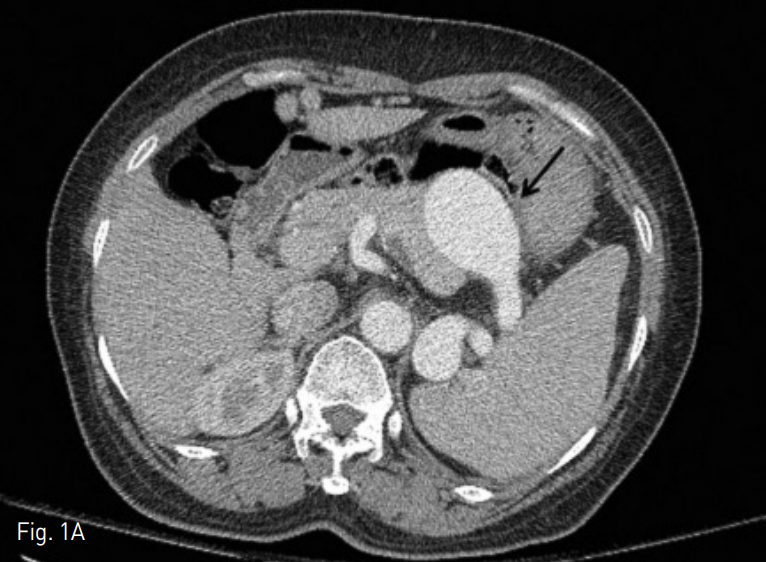

Fig. 1

A. A contrast enhanced axial CT image on arterial phase shows largest splenic artery aneurysm (arrow) with 4.5cm in diameter.

B. A contrast enhanced axial CT image on venous phase shows multiple splenic artery aneurysms (arrow) around splenic hilum.